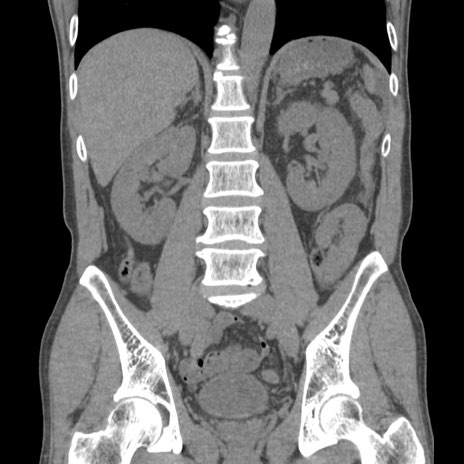

症例56 CT(冠状断像)

横断像